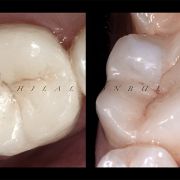

Restoring root canal treated tooth... A Conservative approach!

Based on evidence, all posterior teeth should be restored with cuspal coverage after root canal treatment. However, most of these teeth are badly destructed due to caries or large existent restoration. The key of success is to preserve the remaining tooth structure and restore the tooth conservatively. Dr khalid Merdad and I worked simultaneously to accomplish this task.